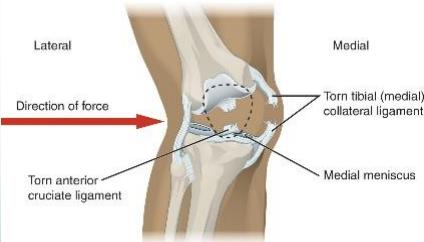

Mechanism of injury:

- Sudden side-way force

- MCL >> LCL (medial collateral ligament is more commonly injured due to anatomical factors)

Medial Collateral Ligament (MCL) Injury

Mechanism:

- Valgus stress to the knee

- Most commonly occurs at medial femoral attachment